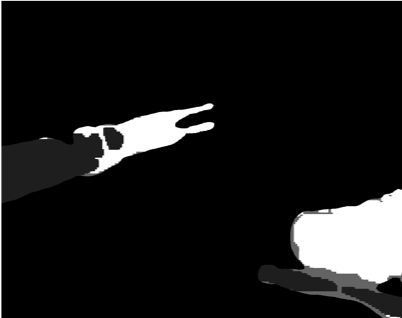

Our challenge was made up of 3 sub-problems. The first was binary instrument segmentation, where each frame was separated into da Vinci Xi instruments and a background class, which contained an ultrasound probe, surgical clips and porcine tissues. The second task was instrument part segmentation, where we scored the participants on whether they could correctly segment each articulating part of the instrument (see Fig. 3). Our final task was to segment and classify the instruments (see Fig. 4).

We provided the first 225 frames of 8 sequences as training data and kept the last 75 frames of those 8 sequences as test data. 2 of the full 300 frame sequences were kept as test sequences. Test labels were kept hidden from the participants. Our datasets contain 7 different robotic surgical instruments. The Large Needle Driver, Prograsp Forceps, Monopolar Curved Scissors, Cadiere Forceps, Bipolar Forceps, Vessel Sealer and additionally a drop-in ultrasound probe, which is typically held in the jaws of the Prograsp Forceps instrument. Samples from the training datasets are depicted in Fig. 2 and examples of the different instrument types are shown in Figure 3 and 4.

Our labelling was performed by a dedicated segmentation team at Intuitive Surgical using the open source software Viame333https://github.com/Kitware/VIAME which provides functionality for frame-by-frame polygon creation. We labelled only the left eye in the stereo pair to reduce labelling time. Labels were provided on an instance level with separate annotated images per object.